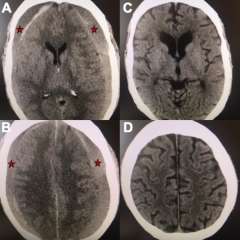

Figure 3

Figure 3. A, B) Axial views of a brain CT scan demonstrating chronic subdural hematomas on both sides of the brain compressing it inwards (red stars mark the hematoma). C, D) Axial views of a CT brain of the same chronic subdural hematoma 3 months after Middle Meningeal Artery Embolization demonstrating resolution of the chronic subdural collection on both sides.